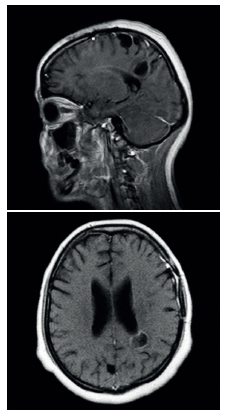

En el control imagenológico con RMN, realizado 12 días después de iniciada la terapia farmacológica biconjugada (Figura 3), se evidenció una clara reducción del volumen de las lesiones, así como un control de la sintomatología referida por la paciente. Además, no se observó elevación de transaminasas, creatinina, ni signos clínicos de intoxicación por cisticidas; motivo por el cual se dio la alta a la paciente, para continuar manejo ambulatorio con albendazol hasta completar 21 días.